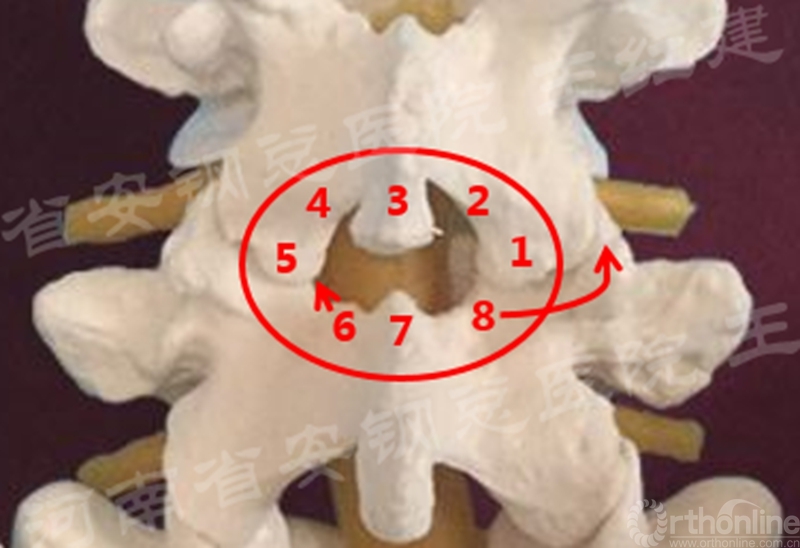

Endo-(P-T)LIF腰椎椎间融合技术四要点

一、入路显露

后侧入路棘突旁开2-4cm;对准正位椎弓根体表投影的猫眼上下平行

临床上,选择存症状重的一侧,自棘突旁2-3cm平椎间隙平面定位,依次递增插入内镜扩张管进行肌肉软组织扩张,最后置入直径12mm工作通道。

二、镜下减压技术神经减压

(1)同侧椎管减压

在进行同侧椎管减压时,重点对侧隐窝及神经根管进行减压,操作中充分暴露上椎板黄韧带起点及下位椎板上5mm,去除肥厚的黄韧带、下关节突及上关节突增生部分。

(2)中央椎管减压

对于中央型狭窄的患者,应向内侧咬除黄韧带至棘突椎板交接处,再将工作通道管向对侧倾斜,将棘突基底部骨质的磨除。

(3)对侧椎板及侧隐窝的处理

在对侧椎板及侧隐窝的处理,潜行咬除对侧椎板深层,可用带保护套的高速小磨钻磨除椎板深层,即将对侧椎板磨薄,将椎管对侧部及对侧侧隐窝扩大成形,咬除对侧黄韧带至硬膜囊对侧外缘处与椎弓根处,根据对侧小关节突增生情况可用磨钻扩大对侧椎间孔与神经根管以解除对侧神经根压迫。

(4) 单侧入路双侧减压

置入内镜通道,用磨钻和枪钳切除上位椎板下缘、下位椎板上缘及突间关节内缘,切除黄韧带,完成单侧入路双侧减压。

单侧入路双侧减压的循序